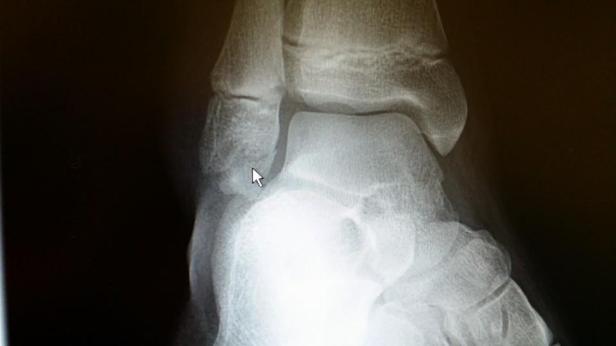

He tells her she will need to get an X-ray (which we already knew and I had already told her that I wouldn’t be able to join her for that, I’d have to wait in the room). He tells her that he’s seen TEN other patients today for ankle injuries and none of them were broken, they were all sprains. But who knows, she could be the one that’s actually broken!

A gal comes and wheels Riley out of the room, and once out of earshot…..he looks at me and says, “It’s broken”. He wants to see the X-ray obviously to confirm, but he says he’s pretty sure it’s actually broken.

When he comes back in and tells her that it’s broken, her world just falls around her.

When it comes to ankle breaks, this was the best possible scenario. The break is well below her growth plate, so it won’t affect her development or growth. And it’s not in a place that will affect her joint at all. And it’s not weight bearing. Yes, it will hurt when she puts weight on it, but putting weight on it will not slow down the healing process and moving her foot around won’t shift the position of the break/bone.